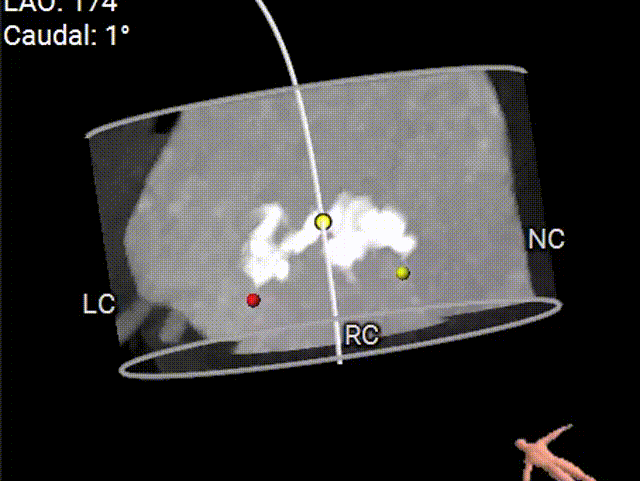

主动脉根部评估

根部概览

Type 0型二叶式主动脉瓣,重度钙化。

多平面分析

敞口状流出道,瓣上限制较重,预估球扩可能存在一定困难。

手术策略分析

Type 0型二叶式主动脉瓣,重度钙化,钙化主要分布在瓣叶边缘,瓣膜锚定力充足,瓣膜形态影响较大;

根据根部及瓣上分析,该患者钙化重,敞口型流出道,瓣上限制较重,采用18mm小球囊预扩,植入TaurusElite AV26型号瓣膜,备AV23瓣膜策略,瓣膜释放后观察形态,必要时采用20或22mm球囊进行后扩;